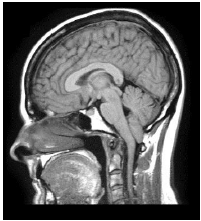

A ressonância magnética de crânio apresenta uma malformação, muitas vezes congênita, capaz de causar sintomas neurológicos como dor cervical; vertigem; perda de equilíbrio; e, disfagia.

Podemos afirmar que tal condição se refere à síndrome de:

Provas